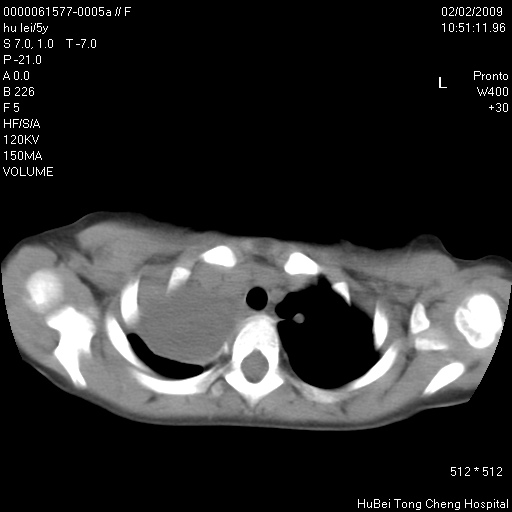

标题: PED1732:M5Y,右肺囊性占位!

患者:男,5。无明显不适,拍胸片考虑右肺囊肿。

行ct扫描,图象如下:

右肺巨大囊性占位性病变;考虑巨大肺囊肿,不排除淋巴管瘤可能。

病灶与前胸壁和右上纵隔、叶间裂界限不清,病灶前缘及内侧缘看不到正常的肺组织,不能排除包裹性积液。